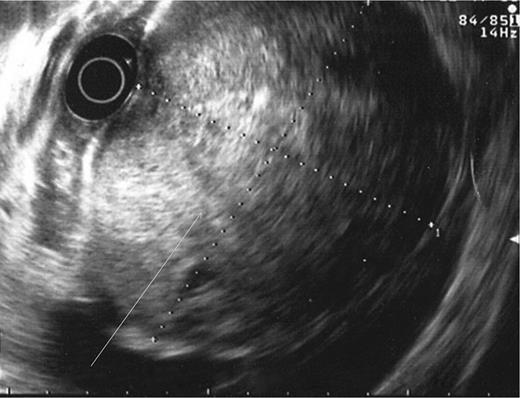

During the second day of admission, the patient passed out large amounts of melena and had an episode of haematemesis. She also developed tacchycardia with heart rate increasing to 110–120 b.p.m. Repeat blood investigations showed that haemoglobin had fallen from 6.8 to 5.3 g/dl despite blood transfusion. An emergency oesophagogastroduodenoscopy was performed. Findings were that of grade 1 oesophageal varices with no features of variceal bleed. There was a large clot in the fundus and cardia of the stomach. After attempted removal of the blood clots with flushing, the patient developed torrential bleeding necessitating intubation for airway protection. The bleeding eventually ceased spontaneously and the source of bleeding was identified to be originating from a large ulcer crater in the greater curve with an overlying clot (Fig. 1). Endoscopic ultrasound was performed which showed a 10 cm mass lesion abutting the stomach wall and extending into the peritoneal cavity (Fig. 2). The preliminary impression was that of a bleeding GI stromal tumour and care was transferred to the surgical team for consideration of surgical intervention.

Endoscopic ultrasound showing lesion abutting stomach wall extending into peritoneal cavity.

Diagnosis of upper GI invasion by HCC causing haemorrhage is difficult and can be easily missed. Radiological imaging may show a bulky HCC invading into the stomach or duodenum, but there have been numerous cases of upper GI tract involvement by HCC which were not demonstrated on imaging [4–6]. Hence, the absence of typical features of tumour invasion in imaging studies does not exclude the pathology. Compared with imaging, endoscopy may better visualize these lesions but HCC invasion of upper GI tract can adopt a myriad of appearances ranging from an ulcerative bleeding mass to a polypoidal or submucosal mass with or without features of extrinsic compression [5]. Thus, it requires a combination of imaging, suggestive endoscopic findings and a high index of suspicion before a diagnosis of HCC invasion causing upper GI haemorrhage can be confidently made. Endoscopic ultrasound may be a useful adjunct as demonstrated in our case. It identified the lesion to be originating from the peritoneal cavity which on hindsight should have led us to consider HCC invading into the stomach as a differential diagnosis in this patient with long-standing liver cirrhosis.